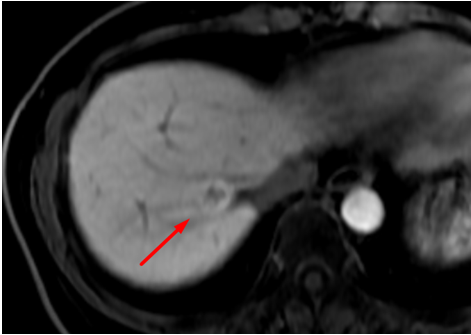

Indeterminate liver lesion on conventional MRI

Liver lesion demonstrating retention of hepatocyte-specific contrast agent in the hepatobiliary phase, suggestive of focal nodular hyperplasia (FNH).